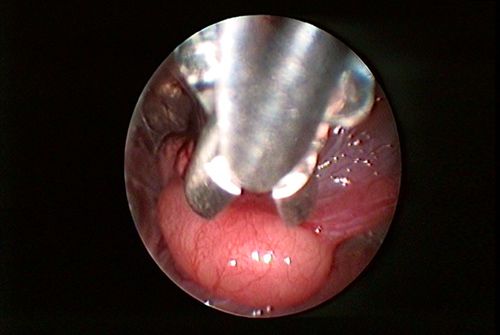

• Biopsieentnahme

Je nach Fall und medizinischer Indikation kann eine endoskopische Biopsieentnahme sehr hilfreich sein. Dabei wird über einen Arbeitskanal eine etwa reiskorngroße Biopsiezange eingeführt, mit deren Hilfe man vom zu untersuchenden Gewebe eine stecknadelkopfgroße Gewebeprobe entnimmt. Anschließend wird diese vom Spezialisten fachmännisch auf eventuelle Abnormalitäten untersucht.